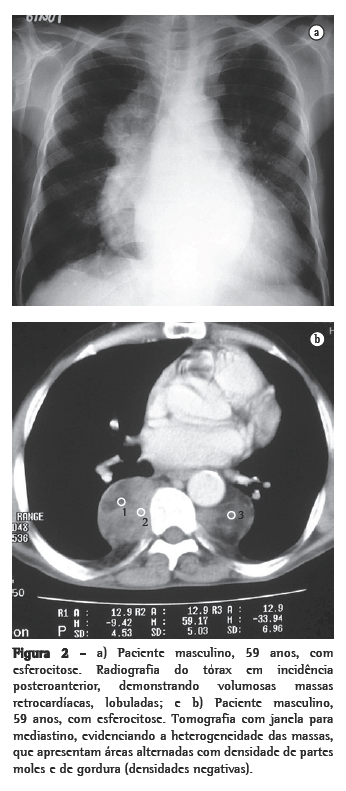

Dos seis pacientes, quatro apresentaram massas paravertebrais inferiores. Em três, elas eram bilaterais e relativamente simétricas, e em um era unilateral, à direita. Quanto ao conteúdo das massas, em três pacientes havia presença de tecido adiposo, sendo que em um desses o material gorduroso era bastante significativo. Em um paciente, as massas eram homogêneas, com densidade de partes moles (Figuras 1a e b, 2a e b).

Radiograficamente, a HEM intratorácica geralmente se apresenta sob a forma de múltiplas massas paravertebrais, com densidade de partes moles, na maioria das vezes bilaterais, lobuladas, com limites bem definidos e sem calcificações ou erosões ósseas associadas.(1,4,5,9) Isso é importante para o diagnóstico diferencial de neurofibromas paravertebrais, que em geral têm alterações ósseas associadas.(4,10) Contudo, evidências de lesões ósseas relacionadas à doença de base são achados comuns. Essas massas geralmente determinam, nas radiografias do tórax, um aspecto de duplo contorno cardíaco, lobulado, na incidência em frontal, assim como um aspecto de massa lobulada projetada sobre os corpos vertebrais inferiores na incidência em perfil.(13)

Através da TC, podem ser observadas massas com densidade de partes moles, em sua maioria homogêneas, com características semelhantes às descritas na radiologia convencional,(1,2,5,6) que podem ou não ser realçadas após a administração do meio de contraste.(4,10) Este método de imagem é importante para analisar a estrutura interna das lesões, particularmente quando ricas em gordura,(5) para avaliar a presença de outras massas paracostais e para detectar alterações ósseas associadas a certas doenças hematológicas, como a talassemia e a anemia falciforme.(6) Nos casos relacionados a talassemia, anemia falciforme ou metaplasia mielóide, pode ocorrer um alargamento das cavidades medulares das costelas.(5)